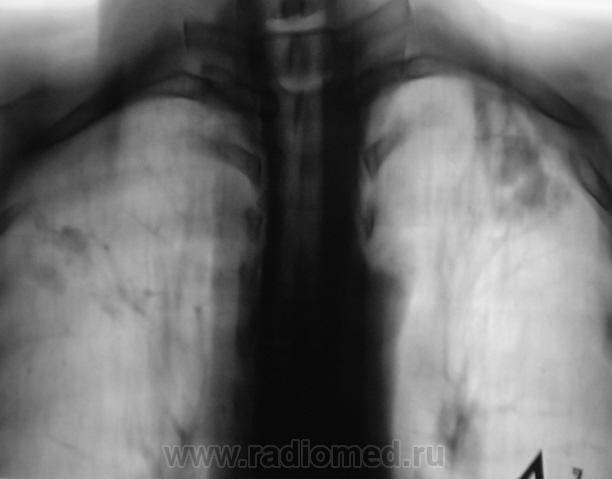

Томограммы.

Я бы остановилась на множественных туберкулемах s1-2 обоих легких,Туберкулемы не однородны.за счет уплотнения,пл очаги.фиброз.

Слева туберкулома и корень подтянут Справа-очаги отсева .Динамика типичная- лечим.лечим-а туберкуломе хоть бы хны!

Действительно множественные туберкуломы, или нет?

Туберкулёма только в С1+2 слева, как дела давно минувших дней.  Произошла реактивация туберкулёзного процесса с развитием двустороннего очагового туберкулёза. Имеется положительная динамика в виду некоторого уплотнения очагов. Таково мое мнение.

<p>Сложно конечно после признанных авторитетов высказываться))) Но, вопросы есть! Почему туберкулема с реактивацией, а не инфильтрация с распадом? Все что высокой интенсивности слева это старые дела, а остальное и справа средней интенсивности неоднородные затенения дела реактивированные?</p>